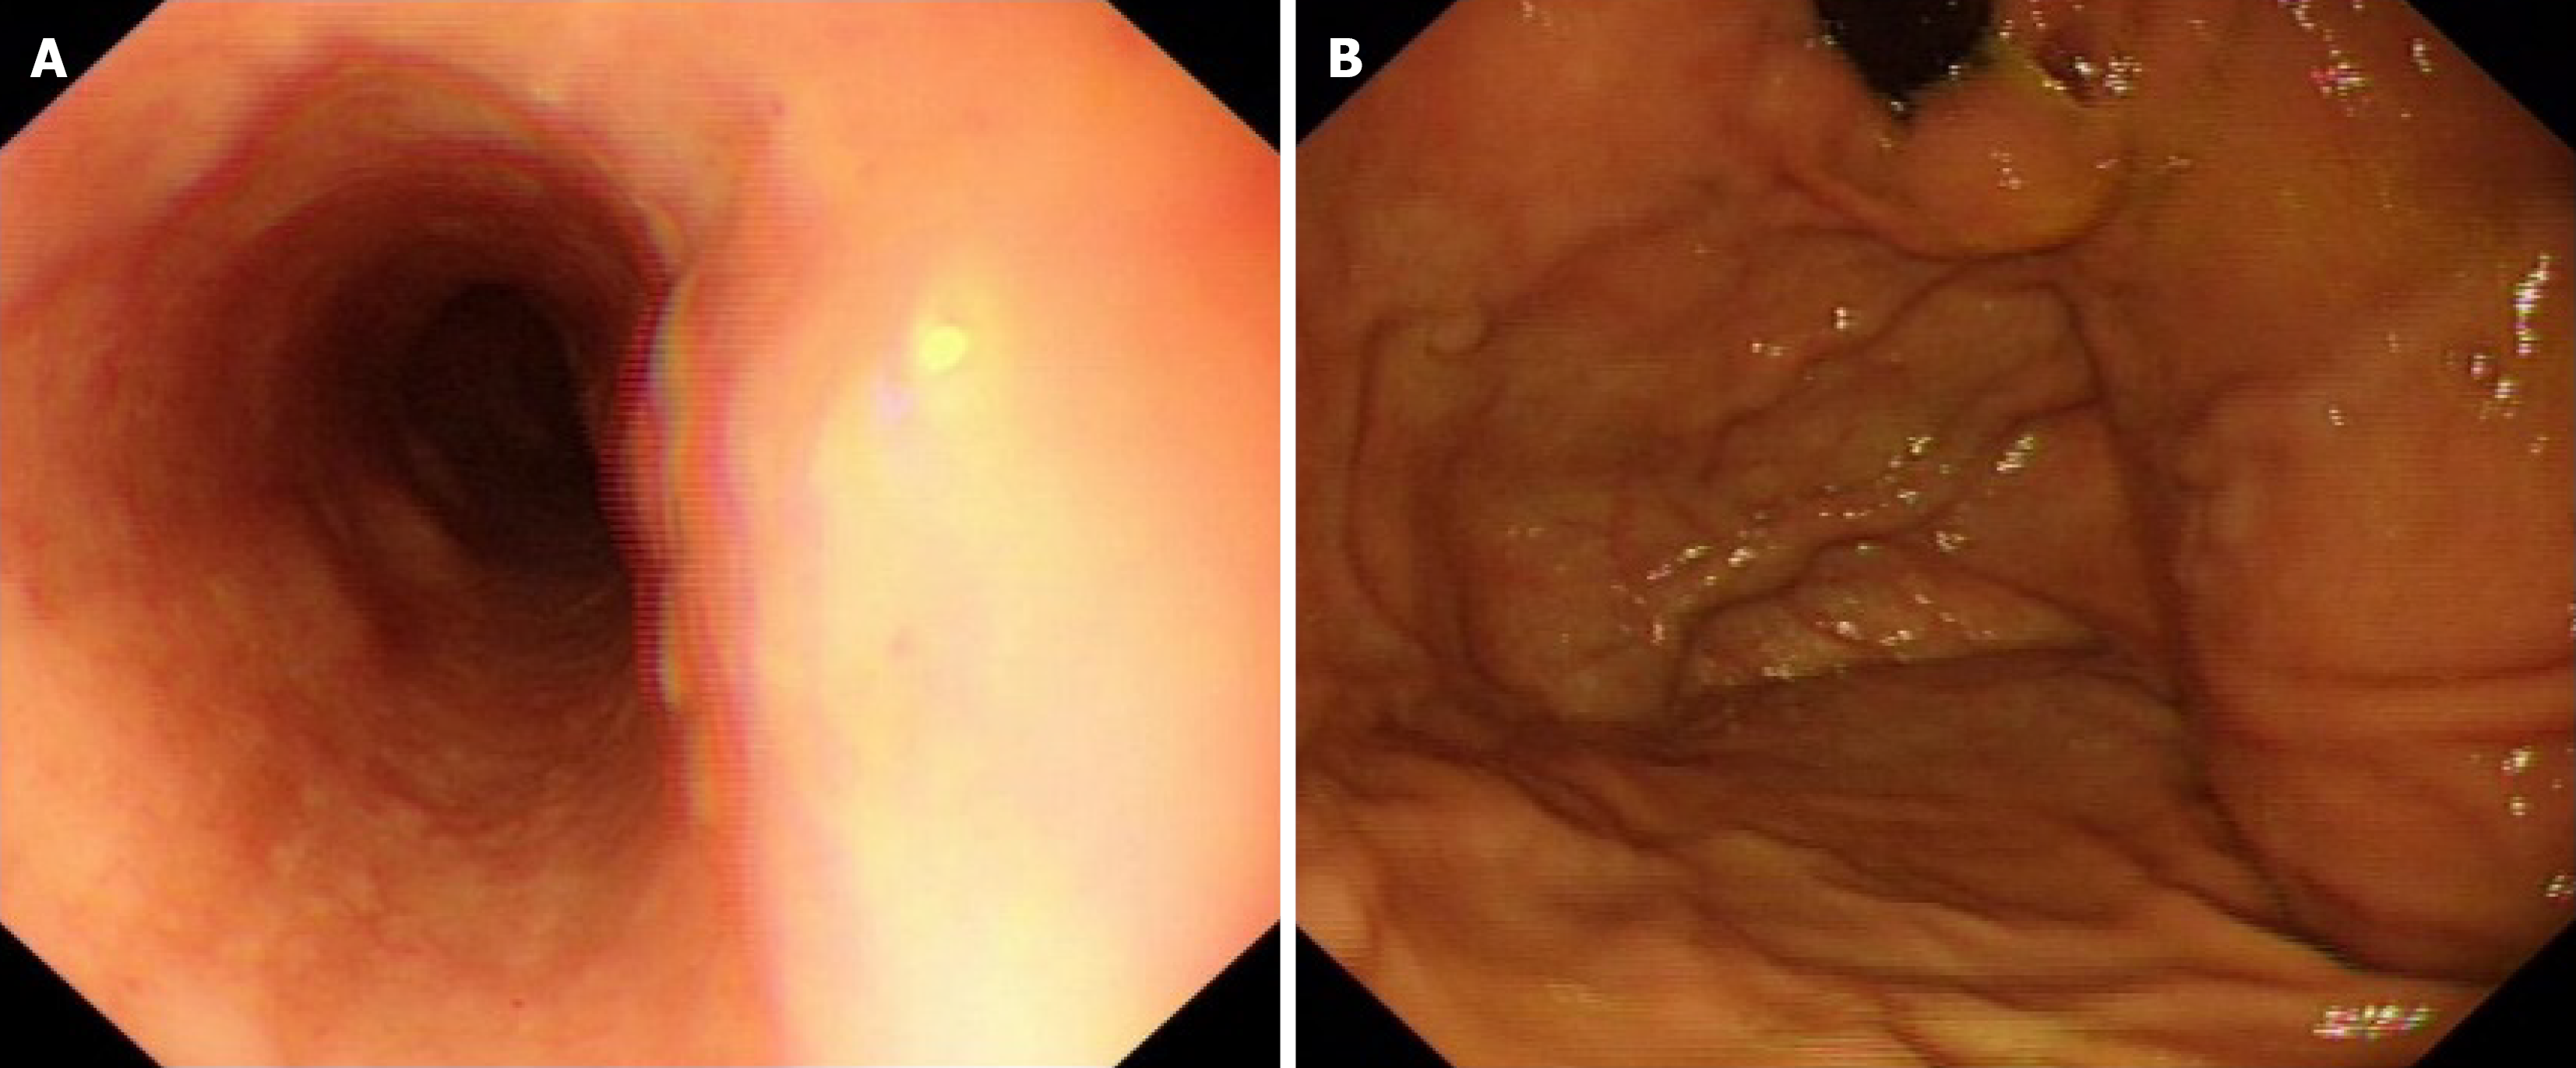

Three months prior to admission, the patient developed unexplained abdominal distension, which persisted despite initial management at a local hospital. One month before admission, her condition evolved to include three episodes of melaena and two episodes of hematemesis with blood clots, accompanied by symptoms of dizziness and fatigue. Subsequent comprehensive evaluation at local hospital revealed a positive hepatitis C cirrhosis antibody result. And the patient received anti hepatitis C virus treatment. Gastroscopy revealed esophagogastric varices (severe RC+), and chronic non-atrophic gastritis with erosion (Figure 1).

One month postoperatively, endoscopic follow-up revealed complete resolution of esophageal varices (Figure 4). No postoperative complications including elevated blood ammonia levels or hepatic encephalopathy were observed during subsequent approximately 5-month follow-up.